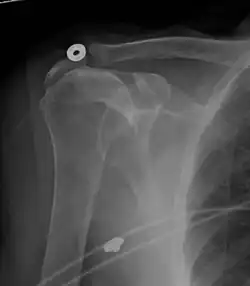

Xray

X-ray projectional radiography cannot directly reveal tears of the rotator cuff, a 'soft tissue', and consequently, normal X-rays cannot exclude a damaged cuff. However, indirect evidence of pathology may be seen in instances where one or more of the tendons has undergone degenerative calcification (calcific tendinitis). The humeral head may migrate upward (high-riding humeral head) secondary to tears of the infraspinatus, or combined tears of the supraspinatus and infraspinatus.[51] The migration can be measured by the distance between:

Normally, the former is positioned inferiorly to the latter, and a reversal therefore indicates a rotator cuff tear.[51] Prolonged contact between a high-riding humeral head and the acromion above it may lead to X-ray findings of wear on the humeral head and acromion; secondary degenerative arthritis of the glenohumeral joint (the ball and socket joint of the shoulder), called cuff arthropathy, may follow.[50] Incidental X-ray findings of bone spurs at the adjacent acromioclavicular joint may show a bone spur growing from the outer edge of the clavicle downward toward the rotator cuff. Spurs may also be seen on the underside of the acromion, once thought to cause direct fraying of the rotator cuff from contact friction, a concept currently regarded as controversial.